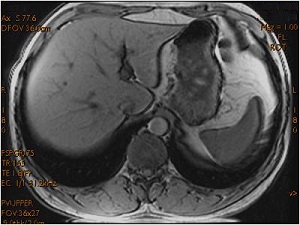

Gradient Echo Chemical Shift artifact

Chemical shift effects are seen when a voxel contains both fat and water and the TE is timed for the vectors to be in or out of phase.

Boundaries between fat and tissues with much water are either bright or dark. For some PSDs, such as FSPGR, the TE can be selected as In Phase or Out of Phase. When In Phase is selected, the fat/water border is bright and when Out of Phase is selected, the fat/water boundary is dark and structures can appear as if they have been outlined with a black marker.

To minimize the black border outline effect, select In Phase as the TE parameter, or manually enter a TE parameter as close to the fat/water in-phase time as possible.